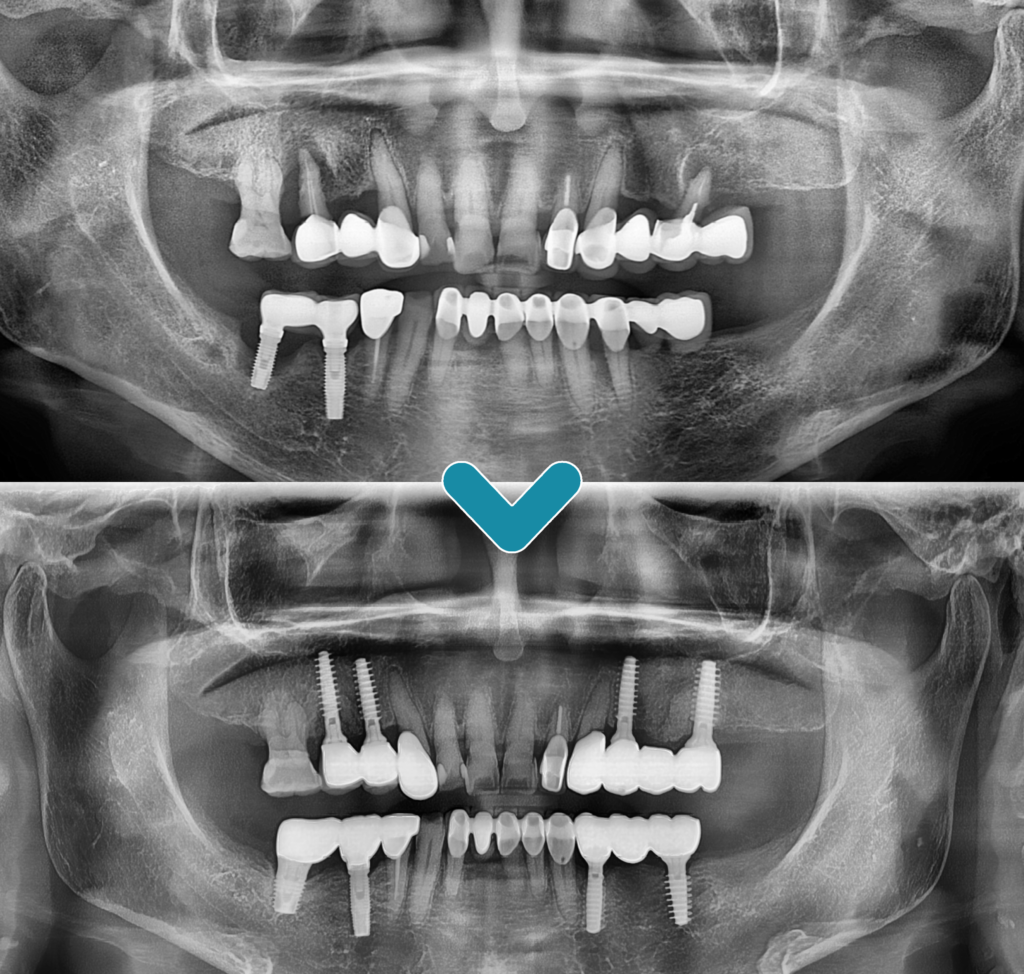

전체적인 파노라마 사진을 촬영한 결과,

왼쪽에서는 이미 어금니가 상실되어

브릿지 형태로 치료가 되어 힘을 받는

치아들의 상태가 좋지 않음을

확인할 수 있었습니다.

오른쪽에서는 기존 아래 임플란트 주위와

위쪽의 자연 치아 주위에서 잇몸뼈가

많이 소실되어 예후가 좋지 않은

상황이 관찰되었습니다.

따라서 예후가 좋지 않은 치아들은

모두 발치한 후 임플란트 식립 계획을

세우기로 했습니다.

환.자분의 구강 상태를 충분히 고려하여

완산구임플란트 치과에서는

매직코어 최소침습 임플란트 수술의 장점을

설명한 뒤 진행하였습니다.

잇몸뼈가 많이 소실된 상태에서도

불리한 조건에도 불구하고,

절개 없이 안정적으로 임플란트 식립을

완료할 수 있었습니다.